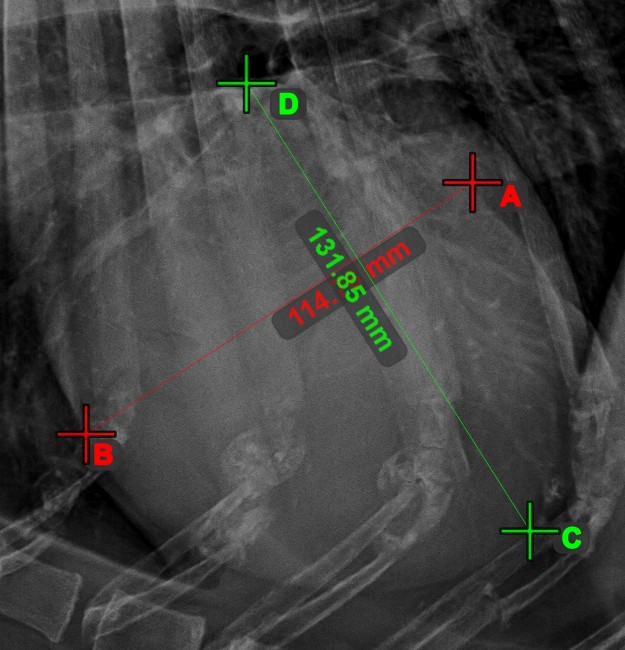

Line Measurement¶

Select the Line Measurement tool and assign it to one of the available mouse buttons. Place the start and end points on the scene or select them from already existing points on the image. The distance between the two points will be automatically

calculated by using the default calibration data, or the recalibrated data by the length calibration measurement.

Modify the start and end point by using the Select/Move Item tool. The distance between the two points will be automatically recalculated.